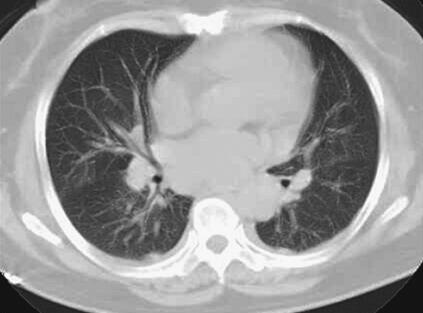

患者,女性,59岁。因“发热8天,上腹部隐痛、腹泻伴胸闷7天”于2011年7月8日入院。患者8天前出现发热,39.5℃,无畏寒、寒战,在当地卫生院予输液治疗(具体不详),症状未好转。7天前出现上腹部隐痛、腹泻,日约4~5次,黄色稀便,伴胸闷,遂就诊于当地镇医院,心电图检查正常,拟“中暑”,予针灸等治疗后无好转。2天前就诊于当地县人民医院,查血常规:WBC 8.4×109/L,N 89.2%,Hb 102g/L,PLT 92×109/L;肥达反应阴性;肝功能:ALT 104IU/L,AST 144IU/L,TP 55g/L,ALB 27g/L;腹部CT:脂肪肝,脾肿大;胸部CT:两肺少许炎症,左侧可疑少许胸腔积液,拟败血症,中毒性肝炎,伤寒住院治疗;期间体温波动于38~39℃,血压波动于80/50~90/60mmHg,予多巴胺[6.0μg/(kg·min)]升压,予亚胺培南-西司他汀钠联合头孢曲松抗感染治疗,病情无好转,仍有发热、腹泻、上腹部隐痛不适,并出现尿量减少、血肌酐升高。于7月8日转笔者医院急诊,测血压[多巴胺6.0μg/(kg·min)维持]89/55mmHg,血常规:WBC 10.28×109/L,N 89.4%;Lac 2.3mmol/L,CRP>90.0mg/L,Cr 141μmol/L,cTnI 6.02μg/L,BNP 577pg/ml;胸腹部CT:两下肺背侧散在炎症,两侧胸腔少量积液,慢肝样病变,胆囊结石(图1、图2);腹部B超:脂肪肝,脾偏大,拟发热待查,心肌炎?感染性休克?,予补液、亚胺培南-西司他汀钠控制感染,多巴胺升血压,为进一步治疗拟上述诊断收入急诊重症监护病房。既往史:40年前发现胆囊结石。

图1 胸腹部CT:两肺纹理增多增粗,两下肺背侧见斑片高密度影,边界模糊;两侧少量胸腔积液(7月8日)

关于恙虫病的肺部改变报道较多。有59%~72%的恙虫病患者可有肺部表现,胸部CT表现可以有磨玻璃影、纵隔淋巴结肿大、小叶间隔增厚、胸腔积液、肺门淋巴结肿大,间质增厚、实变,小叶中心性结节。恙虫病可伴有急性呼吸窘迫综合征(ARDS),是一种少见但很严重的并发症。年龄大、血小板减少、早期肺炎(出现呼吸窘迫前2天,胸片上出现浸润征象)均是ARDS的诱发因素。该患者表现为呼吸促,胸部CT表现为双肺纹理增多、增粗,两下肺背侧见斑片样高密度影,边界模糊;两侧少量胸腔积液,氧合指数<200,考虑并发ARDS。